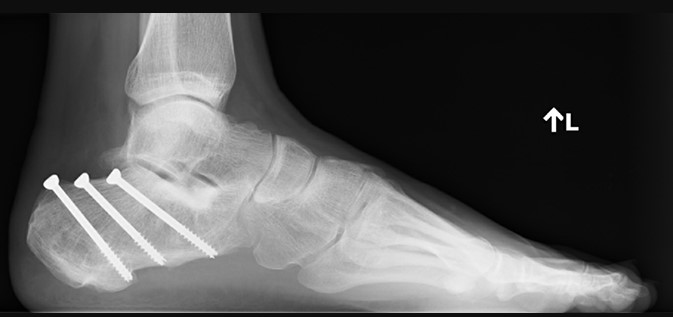

Черезшкірна фіксація переломів пʼяткової кістки — для тих випадків, коли перелом простіший, а ризики відкритої операції занадто великі. Крізь маленькі проколи, під контролем рентгену (ЕОП-у), хірург проводить гвинти, скріплюючи уламки без великих розрізів. Менша травма, швидше загоєння, але й можливості обмеженіші.